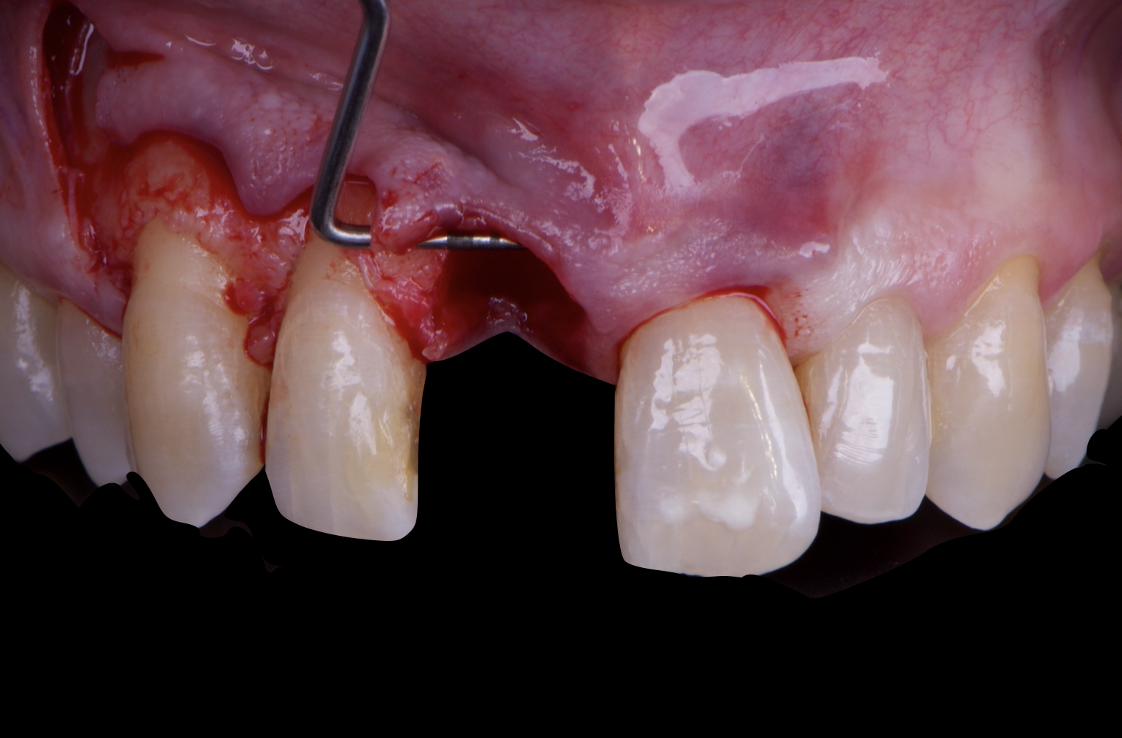

The surgical protocol began with the atraumatic extraction of tooth 1.1 to preserve as much of the alveolar socket as possible. Immediately following extraction, an N1 implant was placed into the socket using a guided surgical approach to ensure ideal three-dimensional positioning. The “one abutment one time” technique was applied to minimize soft tissue manipulation during the healing phase, which is particularly important in esthetic areas.

Given the significant buccal defect, guided bone regeneration (GBR) was performed simultaneously. A mixture of autologous bone and creos™ xenogain™ was applied to the defect and covered with a resorbable creos™ membrane to restore ridge width and support the buccal contour. In addition, a connective tissue graft was harvested and placed in the vestibular region to increase the thickness of keratinized mucosa. This combined approach addressed both hard and soft tissue deficiencies, providing the biological foundation for a stable and esthetic outcome.

On the same day as the surgery, an immediate-load provisional crown was delivered. This restoration was fabricated in acrylic resin and screw-retained on the implant, following the “one abutment one time” principle. The provisional crown was carefully adjusted to avoid occlusal loading while supporting the peri-implant soft tissue architecture during the healing phase.